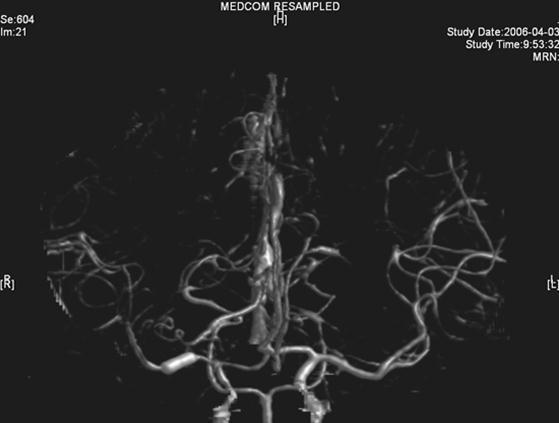

The same dose of aspirin, clopidogrel and subcutaneous LMWH was used after the operation. Two days after the stenting (Mar 23), three successive bouts of left limb weakness along with slight dizziness occurred, lasting about 10 minutes with intervals of 30 minutes. There were no abnormal signs between the first and second attacks. Babinski sign was noted during the second attack and persisted in the left between the second and third attacks with normal muscle strength, but she felt weakness. Blood pressure was 140/70 mmHg. After the third attack, her tongue deviated slightly to the left side. There was slight decrease in muscle strength and Babinski sign was positive in the left. Emergent CT displayed two low density lesions with clear edge and homogeneous density in the right basal ganglia (Figure 3). Aspirin 300mg was given emergently. Compared with the Transcranial Doppler (TCD) test before the operation (March 3), emergent TCD showed the blood flow velocity increased significantly in both anterior cerebral artery (ACA), especially in right ACA (Table 1). She got partial recovery after being given volume expansion treatment with low molecular dextran. Then she was given anticoagulant treatment with intravenous unfractionated heparin (UFH) (500 U/h). LMWH was stopped. On the next day, her muscle strength recovered to normal, but pathological sign persisted. Anticoagulation therapy was continued along with dual antiplatelet therapy. On Mar 25, limb weakness appeared again, muscle strength was Ⅳ grade in the left, both Babinski sign and Chaddock sign were positive. Volume expansion with low molecular dextran was ineffective, and the dose of UFH was increased to750 U/h. Two days later, muscle strength and plantar reflex recovered to normal. On Mar 27, CT scan revealed that the lesion did not change compared with the previous scan, and there was no new lesion. Dose of UFH was reduced to 500H/h. During treatment, blood coagulation test was performed for several times, PT was stabled at 14.1~15.5 sec, APTT at 32.7~43.1 sec, INR at 66.6%~78.8%, activity of antithrombin Ⅲ (AT Ⅲ) at 70.4%~97.2%, and fibrinogen at 3.93~4.68 g/L. UFH was replaced by LMWH on Mar 31. CTA (Apr 3) displayed the stent was in M1 segment of right MCA, its proximal lumen was attenuated compared with the left MCA, with slightly compromised distal blood flow (Figure 4).

The right MCA stenosis, which led to the transient ischemic attack (TIA) symptoms, was definitely diagnosed. Angioplasty and stenting was conducted after full preparation of dual anti-platelet therapy. Immediately before the operation, LMWH was used in combination and was continued after operation. Her condition was stable in the first two days after operation. Then crescendo TIA recurred and led to motor impairment. Two lesions were shown in the emergent CT images. One was near the anterior horn of the right lateral ventricle, by which it was difficult to explain the symptoms and physical signs. The other was in basal ganglia, and was related to the symptoms and signs. The signal in this region had been slightly higher than the counterpart in the left in the source image of MRA before operation. Hence the lesion in basal ganglia was thought to result from hemodynamic impairment in distal parts of stenotic MCA. Both lesions had clear boundaries, which indicated that the infarction in the area supplied by deep branch of MCA occurred before the TIA attacks. The crescendo TIA worsened gradually, but got partial recovery after volume expansion treatment initially. TCD test showed the blood flow velocity increased in both ACA, especially in the right, while that in the right MCA did not significantly increase. This indicated that some collateral circulation had formed, to counteract hypoperfusion caused by progressive stenosis in the right MCA. Based on these, we deduced that there was IST which did not completely block the right MCA. The symptoms and physical signs appeared again when there was failure of collateral compensation. Because there were new lesions on CT scan and the patient had been treated with dual anti-platelet treatment and anticoagulation, thrombolytic therapy could not be given. So we gave unfractionated heparin (UFH). The symptoms and physical signs disappeared on the next day. But two days later during the same treatment, the symptoms and signs recurred, volume expansion was ineffective, this indicated that initial recovery of symptoms was due to compensatory collateral circulation, and anticoagulation therapy with UFH may also play a role. But this could not prevent thrombosis from progressing, so we increased the dose of anticoagulation drugs, the symptoms and signs disappeared eventually. CTA (Apr 3) and repeated TCD (Apr 17) confirmed our reasoning with attenuated proximal lumen of right MCA and increased blood flow velocities of the right MCA and ICA.